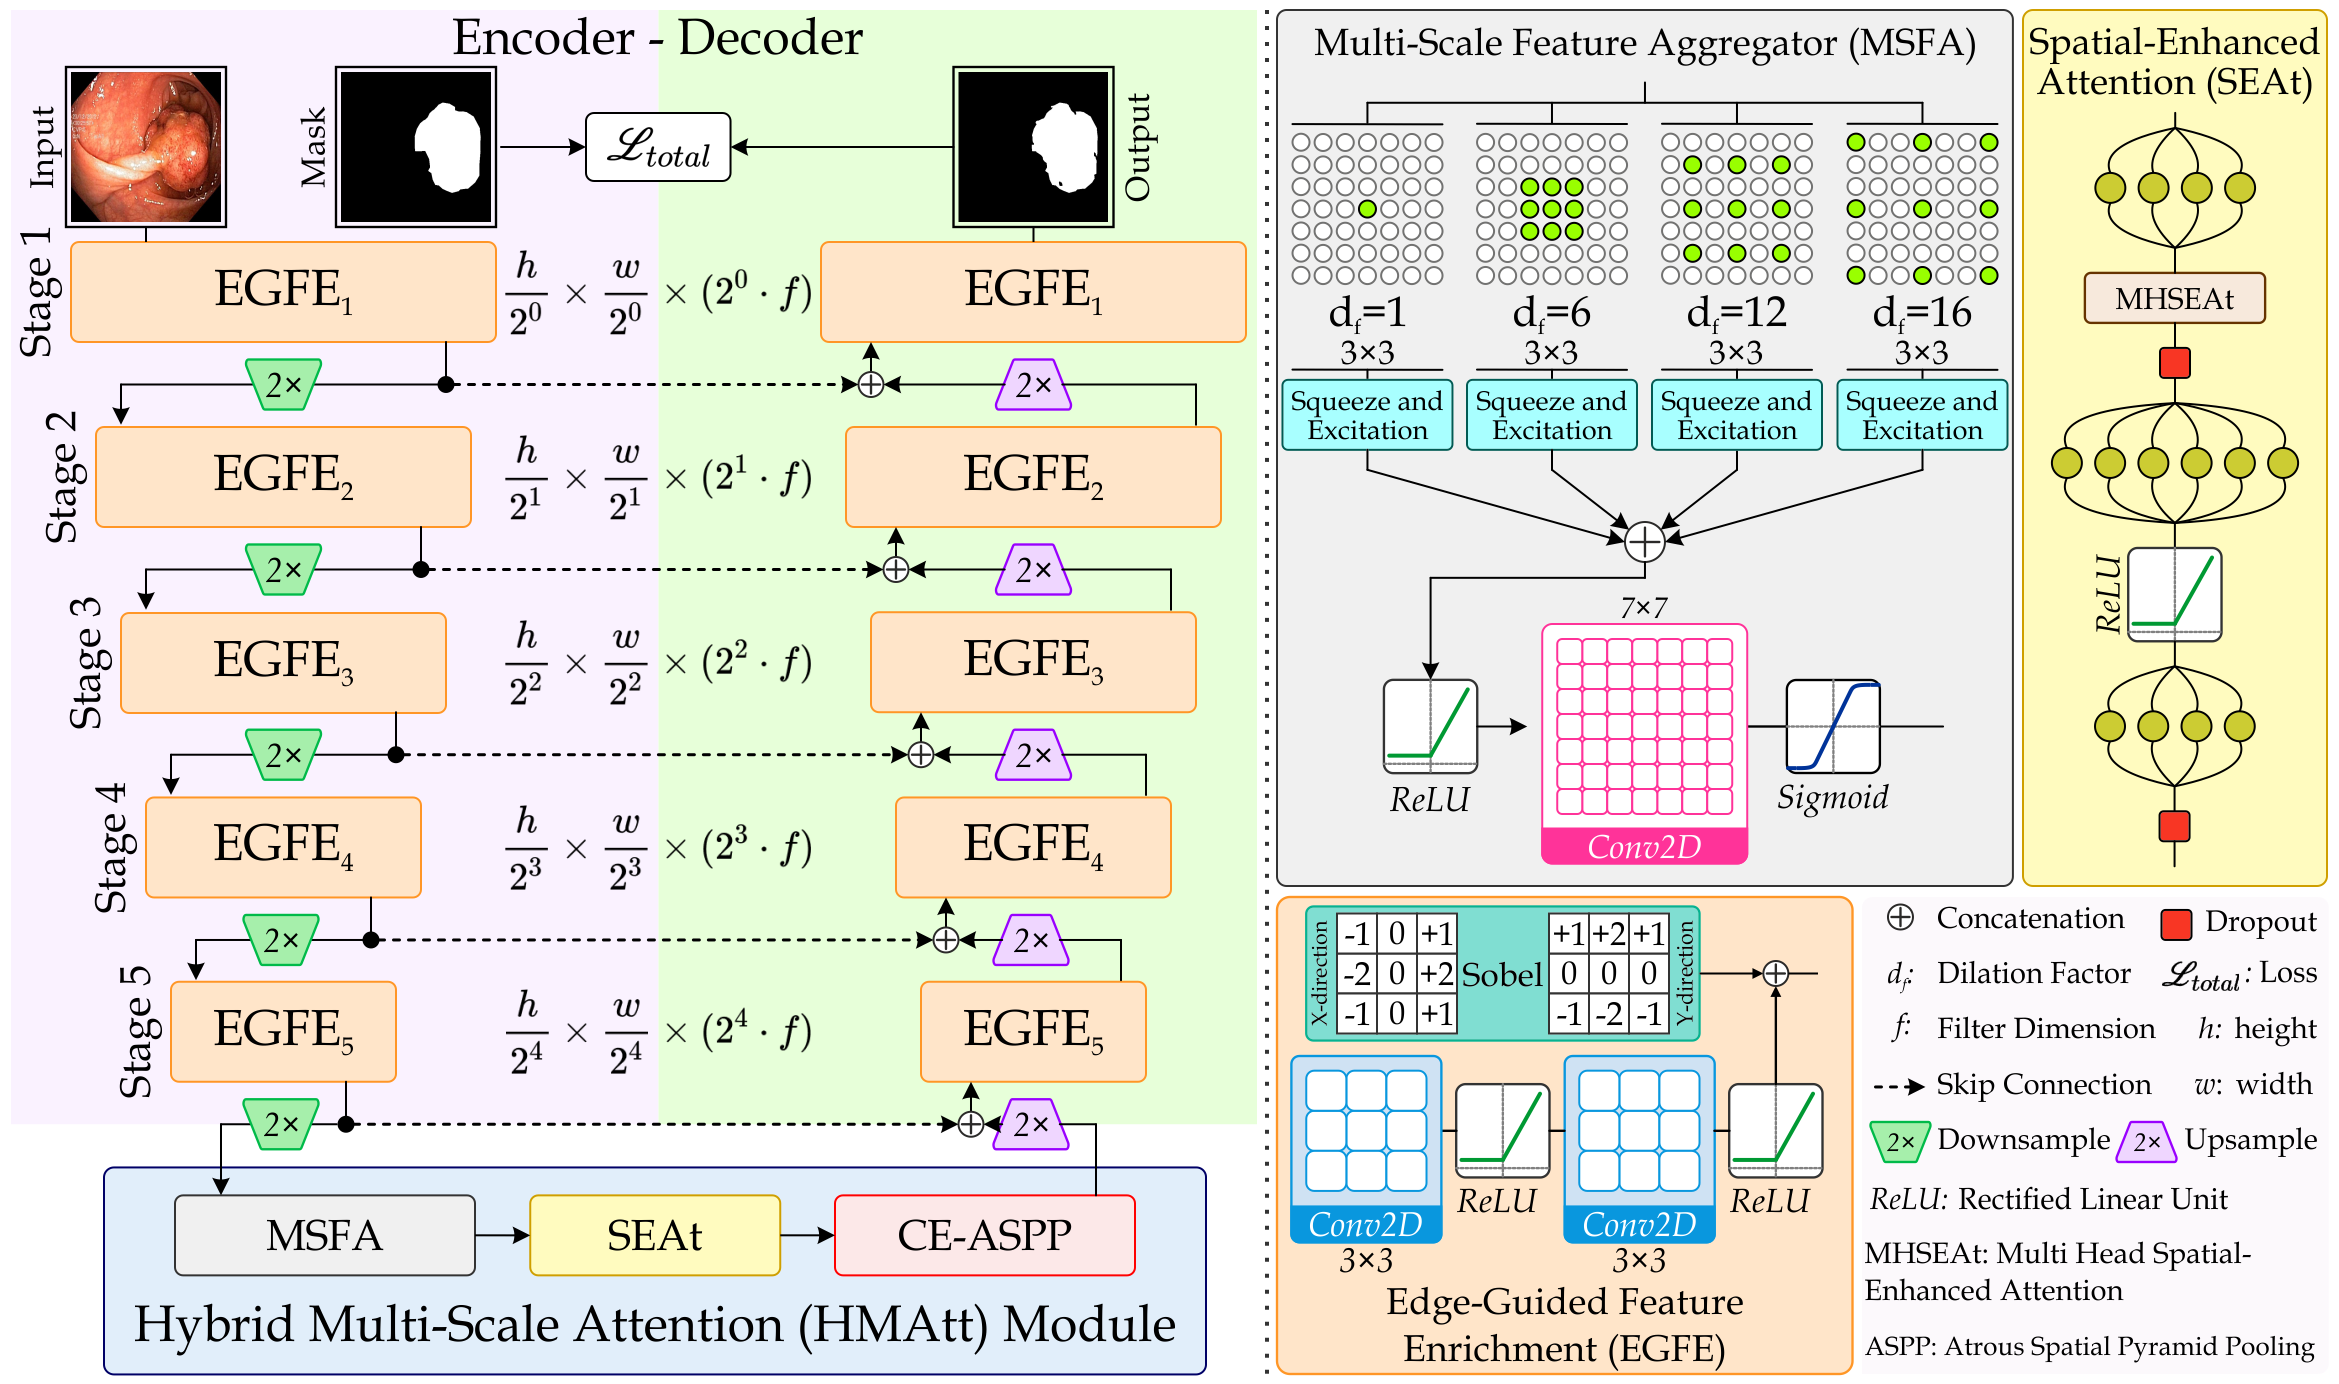

The MNet-SAt framework illustrated in Fig. 2 adopts a U-shaped architecture with an encoder and decoder pathway linked through skip connections. The encoder downsamples input data of dimensions using convolutional layers, while the decoder restores the data to its original dimensions. Each encoder stage downscales features to dimensions of . Key components of this framework include the Edge-Guided Feature Enrichment (EGFE) unit and the Hybrid Multi-Scale Attention (HMAtt) module. The EGFE unit integrates edge-aware feature extraction and enhances boundary-aware feature representation, improving segmentation performance. The HMAtt module employs multi-scale receptive fields to enrich the extracted features, enhancing the framework’s adaptability. Additionally, the framework achieves precise anomaly localization and segmentation by focusing on critical regions. Finally, a convolutional layer with an appropriate activation function processes the aggregated features from the decoder’s last stage to compute segmentation probabilities.

3.2 Encoder-Decoder Backbone

Our MNet-SAt framework utilizes a U-shaped backbone structured with an encoder and a decoder, each containing five Edge-Guided Feature Enrichment (EGFE) units designed to generate feature maps rich in edge information. To incorporate boundary cues, we apply a Sobel operator before the convolution within each EGFE unit. This enables the separate learning of coarse boundaries and effective edge features. In the encoder path, a downsampling operation (reducing resolution by ) precedes each stage to progressively reduce the feature map size and feed it into the next encoder. The decoding path commences from the output of the HMAtt module, a multi-scale attention network that facilitates communication between the encoder-decoder pair. The decoder pathway in MNet-SAt leverages encoder features provided by the EGFE units to generate segmentation masks. Decoding blocks upsample their outputs by before concatenation with corresponding encoder feature maps. We then feed the concatenated features from multiple stages into subsequent decoding blocks for further refinement. Finally, we upsample the last stage’s feature map to match the input dimension, incorporating information from the encoder and decoder. Table 1 details the feature map dimensions for each stage in the encoder and decoder.

3.3 Edge-Guided Feature Enrichment Unit

The scarcity of annotated data in clinical practice hinders existing methods’ ability to capture polyp boundaries accurately. To address this, we propose the Edge-Guided Feature Enrichment (EGFE) unit, designed to enhance boundary quality in segmentation masks. EGFE robustly preserves edge information, mitigating the issue of weak boundaries, bridges the semantic gap between low-level and high-level features, and directly captures spatial features of polyps from input images. A pre-processing step incorporating a 2D Sobel operator [32] ensures the preservation of crucial edge details during convolutions.

The Edge-Guided Feature Enrichment (EGFE) unit actively enhances feature representation by integrating edge knowledge into the set of features. It applies a Sobel operator to the input feature set, generating separate gradient magnitude maps for horizontal and vertical directions (Fig. 3). As illustrated in Fig. 3, the Sobel operation in a single direction captures limited information about the polyp. However, combining these maps (Fig. 3(d) and Fig. 3(h)) effectively captures polyp boundaries and enriches learned features. The final gradient magnitude map, produced using the Euclidean norm (Eq. 1), highlights regions with significant intensity changes at polyp boundaries.

3.4 Hybrid Multi-Scale Attention Module

The MNet-SAt framework utilizes a Hybrid Multi-Scale Attention (HMAtt) module to bridge encoder-decoder backbone. HMAtt effectively captures multi-scale contextual information and highlights salient regions within feature maps.

3.4.1 Multi-Scale Feature Aggregator Unit

Colonoscopy image analysis often assumes that specific features reside at specific scales [33]. However, existing multi-scale approaches primarily focus on feature extraction [33], neglecting aggerated channel-spatial dimensions. To mitigate this, we introduce a Multi-Scale Feature Aggregator (MSFA) Unit that integrates Squeeze-and-Excitation (SE) blocks [29] after multi-scale feature extraction and aggregates them. This emphasis on salient regions enhances the polyp’s feature representation.

The MSFA unit receives the output of the encoder’s final EGFE unit, , as input. It then processes this feature map through multiple convolutions with varying dilation rates, as defined mathematically in Eq. 3.

3.4.2 Spatial-Enhanced Attention Unit

As illustrated in Fig. 2, the Spatial-Enhanced Attention (SEAt) unit, a core component of the HMAtt module, captures spatial-aware global dependencies within the multi-scale aggregated features derived from the MSFA unit. The SEAt comprises a Fully Connected (FC) layer, MHSEAt, feed-forward layers, and a dropout layer. Due to the pivotal role of the attention mechanism within SEAt, we provide a detailed introduction to MHSEAt below.

Multi-Head Spatial-Enhanced Attention (MHSEAt): The Multi-Head Spatial-Enhanced Attention (MHSEAt) performs the self-attention operation along the spatial dimension. As shown in Fig. 4, firstly, the three identical copies of feature maps are normalized through Layer Normalization , followed by convolution operation with kernel having dilation rate of . Next, the spatial-enhanced features are aggregated with Global Average Pooling to obtain the Query (), Key (), and Values (). We can formulate the process mentioned above as follows: